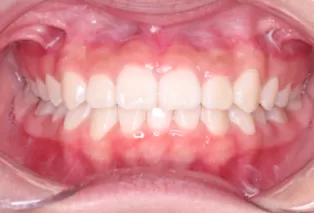

Intraoral photos